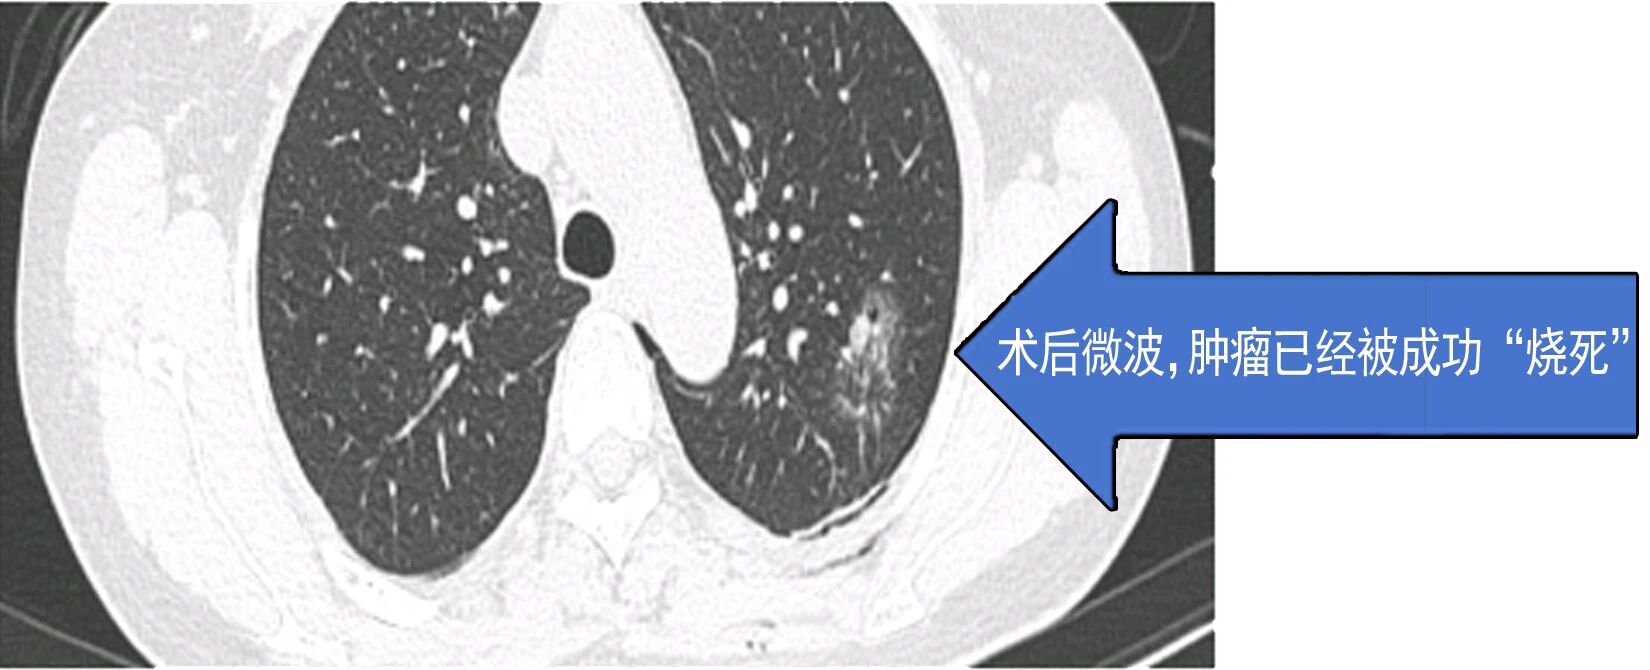

患者因肺结节就诊后,术前检查提示传统手术可能造成较大肺功能损伤,患者及家属因此产生明显焦虑情绪。胸外科团队综合评估病情后,决定采用微波消融技术施治。手术依托CT实时导航技术,将消融针精准送达结节部位,误差控制在3毫米以内,仅通过一个针孔创口完成操作,单次消融过程耗时5-10分钟,患者3天内出院,健康肺组织功能得以保留。

据悉,微波消融技术虽有微创优势,但不能替代传统根治性手术——对于可耐受手术的早期肺癌患者,手术切除仍是临床金标准。该技术更适用于直径≤3cm的孤立性周围型高危小结节、数量≤5个的多发结节患者,以及心肺功能差、无法耐受手术的高龄高危人群,同时可作为拒绝手术者、术后复发或残留结节患者的辅助治疗方案。 技术突破背后,离不开医院完善的硬件支撑与多学科协作机制。术前需经多学科团队(MDT)严格评估,确保患者符合适应症要求。胸心外科始终坚持肺结节治疗“量体裁衣”原则,强调早发现、早干预与规律随访的重要性,未来将进一步探索微创与微波技术的联合应用模式,持续提升肺结节诊疗精准度与患者就医体验。